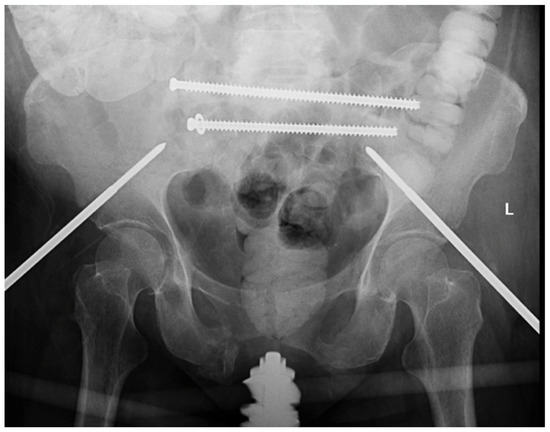

Prior lateral hip incisions were reopened and enlarged to gain access to the posterior sacral hardware. Both existing screws were recannulated with wires, and the S2 screw was removed and replaced with a new Synthes 130 mm fully threaded 7.3 mm cannulated screw, which achieved moderate purchase. The S1 screw was removed; however, the standard washer was determined to be too small, risking propagation of the fracture. Instead, a mesh plate from the Synthes Variable Angle Midfoot set was chosen to act as the washer and cut to 3 × 3 holes. The larger surface area of the mesh plate allowed for increased bony interface of the construct, thus distributing the forces and decreasing the risk of fracture propagation while also increasing stability. The middle hole of the plate was placed over the S1 wire, followed by a standard washer, and the Synthes 165 mm fully threaded 7.3 mm cannulated screw (Figure 5). This combination of hardware achieved excellent purchase and re-established stability of the right posterior pelvis. Alignment was confirmed with intraoperative fluoroscopy. There were no obvious perioperative complications, and the patient was transferred to the PACU.

Figure 5.

AP pelvis demonstrating trans-iliac trans-sacral screw placement at the S1 and S2 level with the use of a midfoot plate as a washer on the S1 screw.

Revision surgeries in the case of failed fixation for sacral fractures present a unique challenge. Getting an appropriately stable fixation while also being attentive to patient safety and avoiding neural injury is of the utmost importance. We present a case of a patient who sustained a highly displaced and translated sacral fracture treated with surgical fixation via a novel technique: a Synthes cannulated screw and washer combination wherein a tailored midfoot mesh plate was used as an additional washer for superior fixation. Upon hardware removal and revision, internal fixation was accomplished via Synthes cannulated screws and midfoot mesh plate as a washer. At 3 months of follow-up, fracture union was achieved, and the patient was able to return to weight-bearing with the assistance of an ambulatory device. It should be noted that the delay in recovery was primarily due to the lack of motor function of the right foot.